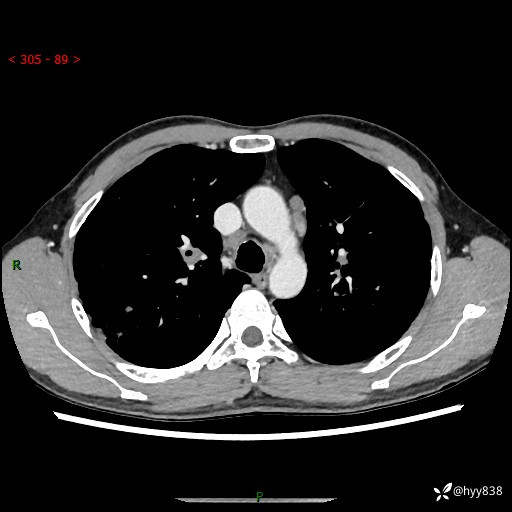

中年男性,咳嗽咳痰1月余。细看:肺、肺门、气管,貌似都有问题---(有结果)

现病史:患者于1个月前受凉后出现间断性咳嗽,伴白色泡沫样痰,无发热寒战、咯血、胸痛胸闷、恶心呕吐、呼吸困难等特殊不适,起初未予特殊处理,后患者就诊当地中医医院,查胸部CT提示支气管炎并双肺感染性病变,经抗感染(哌拉西林舒巴坦),止咳化痰(溴己新、三拗片)等治疗后,患者自诉咳嗽咳痰症状较前缓解,未诉发热等其他特殊不适,近期复查CT提示“肺部感染灶未见消退,双侧肺门增大,双肺散在小结节”,今为求进一步诊治,前来我院就诊,门诊以“肺部感染”收住入院。 患者自起病来精神、食欲、睡眠尚可,大小便正常,体力、体重无明显变化。

胸部CT平扫+增强(两期)